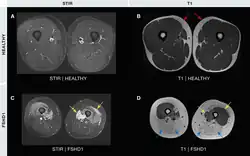

Examples of MRI imaging in FSHD. The white within the muscles of the STIR (T2) image represents muscle edema. The white within the muscles of the T1 images represents fatty infiltration.

Medical imaging (CT and MRI) have shown muscle involvement not readily apparent otherwise[37]